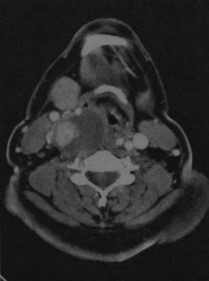

КТ с контрастированием : рак щитовидной железы на уровне щитовидного хряща справа. Опухоль имеет сложную структуру и включает зоны некроза, имеющие пониженную плотность, участки кровоизлияний, имеющие повышенную плотность и участки с интенсивным усилением после введения контраста. Опухоль смещает вперед гортань и нервно-сосудистый пучок. Кпереди от опухоли заметен дефект кожи.

КТ с контрастированием: обширное вертикальное распространение рака щитовидной железы в направлении головы. Опухоль содержит кистозные участки сниженной плотности, зоны кровоизлияний, имеющие повышенную плотность, и участки интенсивного усиления. В правой поднижнечелюстной области непосредственно кпереди от опухоли определяются крупные метастазы в лимфатические узлы.